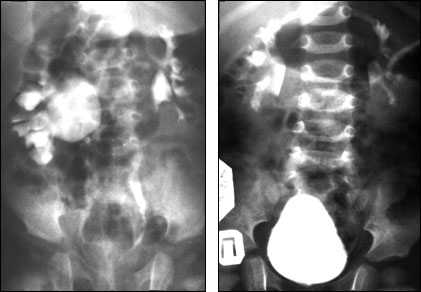

Рис.15. Рентгенограмма ребенка с гидронефрозом справа (абберантный сосуд). Тот же больной через 1 год после операции.